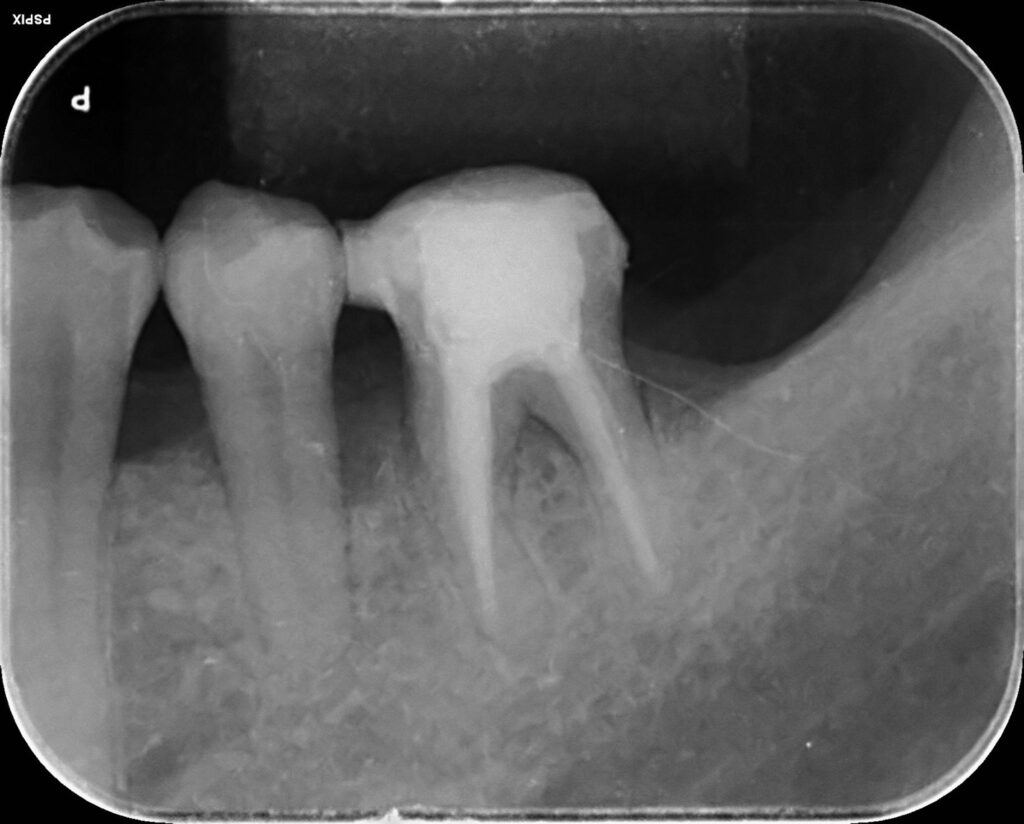

- 精密な検査(ポケット検査・レントゲン・CTなど)

- 歯周病専門的な診断

- マイクロスコープでの状態把握